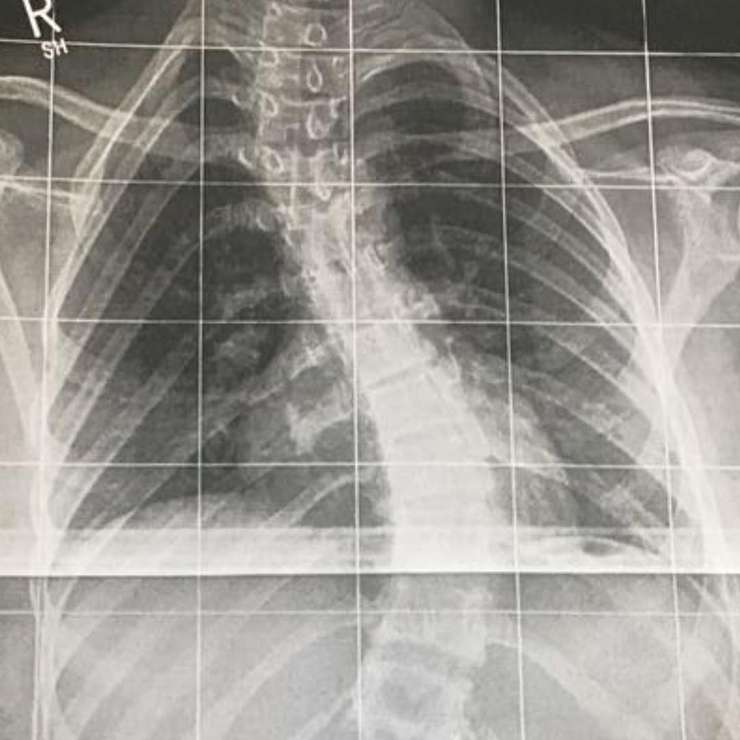

Во время майских праздников актриса Елена Воробей напугала поклонников, сообщив, что ее дочь попала в больницу в Германии. Долгое время от артистки не было вестей: она почти ничего не писала о произошедшем в своем «Инстаграме» и не давала комментариев. К счастью, на днях стало ясно, что же произошло. Оказалось, что ребенок был вынужден лечь в больницу на операцию, по сути, по вине российских врачей. Девушке в немецкой клинике сделали операцию на позвоночнике. Об этом артистка рассказала в своем микроблоге, выложив рентгеновский снимок. Елена поведала, что обратилась в клинику в Москве, где ребенку был поставлен диганоз — сколиоз, причем в довольно серьезной форме. Однако, когда позже мама с дочкой снова пошли ко врачам, чтобы взять освобождение от физкультуры, в больнице сообщили, что сколиоз неожиданно… пропал! «Вот с такой спиной нам не дали освобождение от физкультуры и сказали, что я „придумываю“ проблему, которой нет, что это сколиоз минимальный, и нечего отвлекать врачей по пустякам!!!!» — писала артистка в своем микроблоге.

Однако около полугода назад у Сони появились страшные боли, ей стало тяжело дышать, тогда Елена поняла, что не хочет испытывать судьбу во второй раз, и обратилась к немецким специалистам, которые посоветовали не затягивать с операцией, потому что ситуация ухудшалась буквально с каждой неделей. В итоге дочери Елены сделали операцию, поставили в спину 20 шурупов. Правда, о том, каково сейчас состояние девочки, Воробей толком не рассказывала, а в последние три дня она вообще перестала обновлять соцсети, чем напугала своих подписчиков.